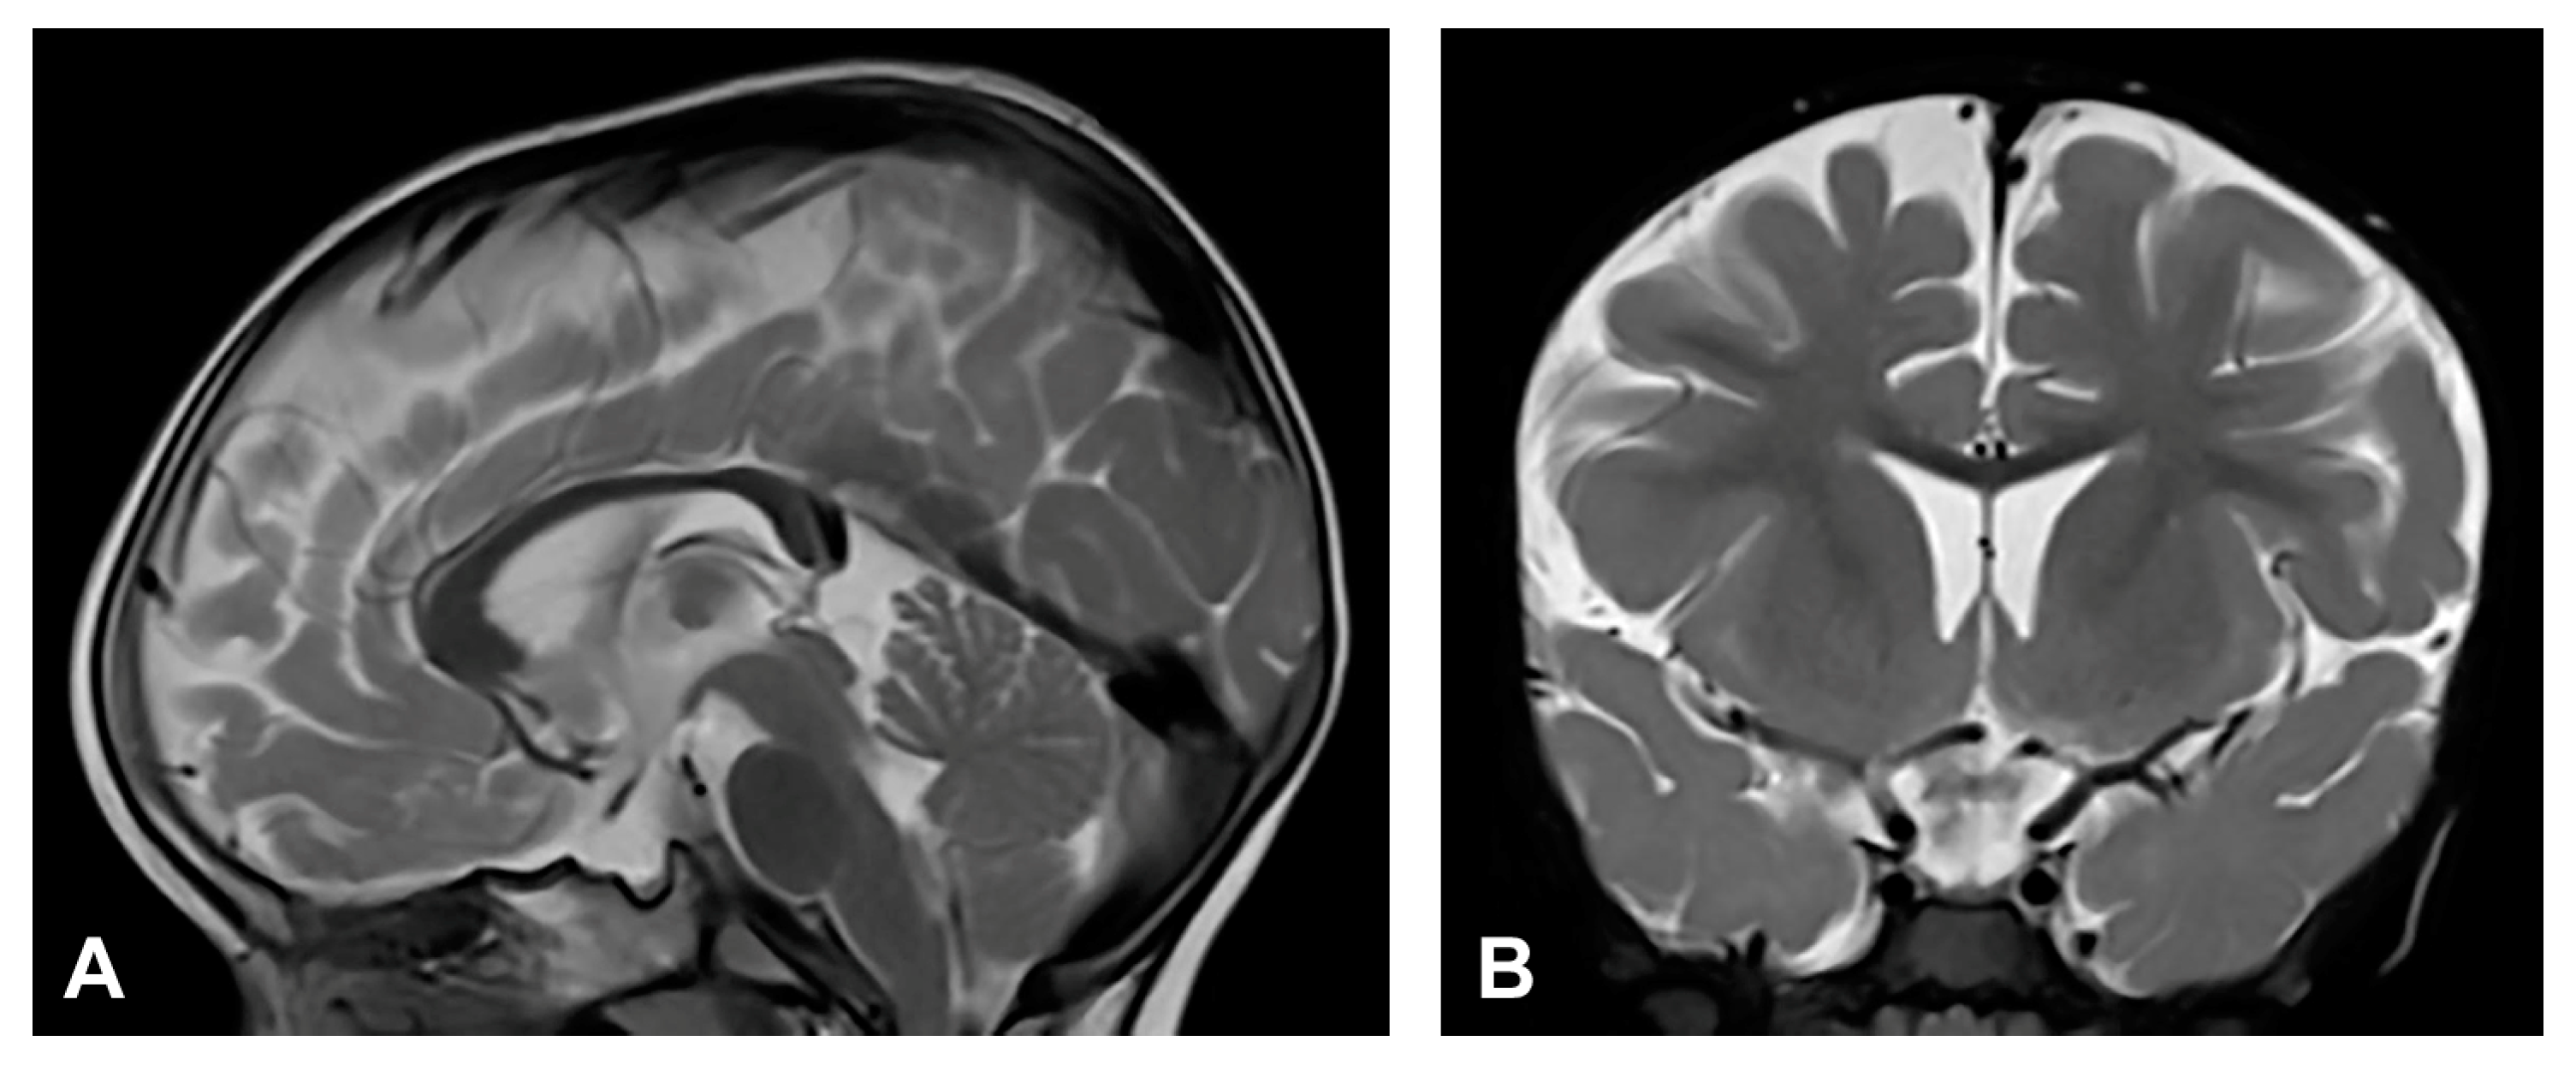

The patient was one and a half months old at the initial visit, presenting hyperpigmented macules following Blaschko lines and a few verrucous papules. Two biopsies were performed depicting stage II and III of IP. After six months, skin changes were at stage III. As in previous stages, the affected area was devoid of terminal hair. The patient was diagnosed with retinopathia ischemica proliferativa. The patient also presented a gothic palate, delayed eruption and peg-like teeth. At the age of six months, the neurological examination revealed mild hypertonia, symmetrical motor activity and brisk deep tendon reflexes. The patient achieved slightly delayed developmental milestones, starting to walk without support from the age of two. Speech development was also mildly delayed. MRI showed no pathological findings (Figure 4).

Figure 4.

(Case 4) (A) Sagittal and (B) coronal T2W magnetic resonance images at the age of nine months without pathological findings.